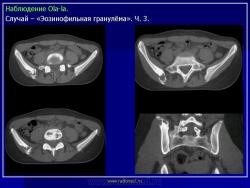

Из опубликованных наблюдений н сайте.